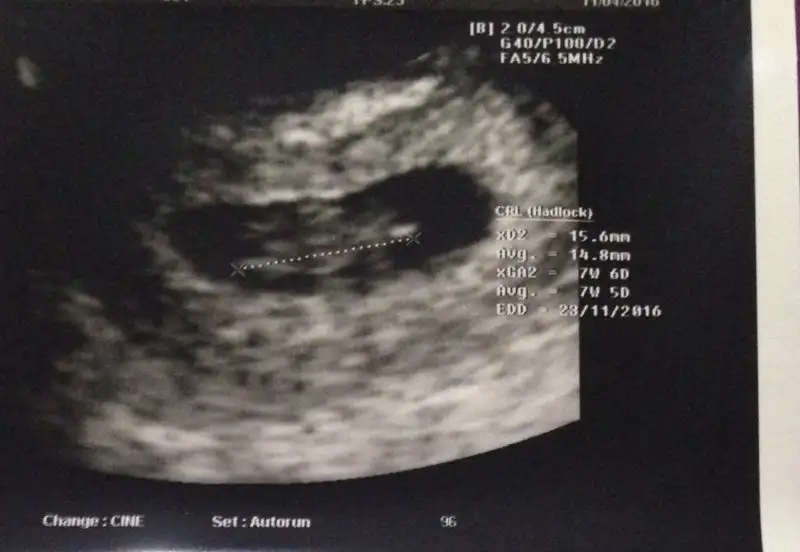

12+2 digeri 11+6 gittim doktor soylemedi 14+4 digeri 14+1 olduk 16 haftayi bekliyorum canim saglikla nasip etsin rabbim cumlemize insallahAynen öyle yaâsizin cinsiyet belli mi artık :)